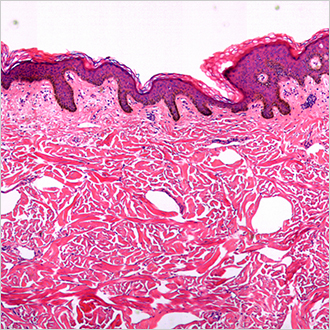

TM-Microscopy

Questa soluzione ottimizza la distribuzione e l'accesso a immagini anatomo-patologiche, con possibilità di richiamo, memorizzazione ed analisi delle stesse con il visore TM-Microscopy. Offre risultati diagnostici di alta qualità per la maggior pertinenza delle analisi dei campioni e le funzionalità che facilitano lo scambio di opinioni tra patologi. Leggi tutto?